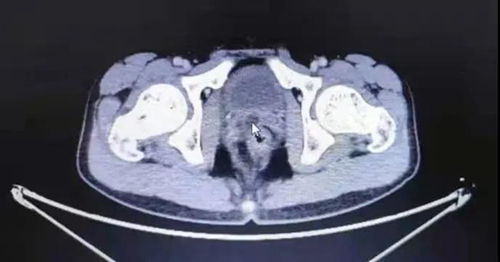

CT顯示,在孩子本就狹小的膀胱和直腸間隙中尋找直徑僅1.4cm的腫物,難度非常大。這塊“攔路石”究竟該怎么掏?

泌尿外科團(tuán)隊(duì)專家反復(fù)討論,決定先使用膀胱鏡進(jìn)入尿道探查,再聯(lián)合腹腔鏡尋找并切除腫物的微創(chuàng)技術(shù)。

手術(shù)如期進(jìn)行,團(tuán)隊(duì)成員使用膀胱鏡聯(lián)合腹腔鏡進(jìn)行探查。通過肚臍上開的小孔,手術(shù)醫(yī)生操作腹腔鏡繞過懸吊的膀胱進(jìn)入盆腔,穿過膀胱和直腸狹小的間隙,避開輸精管和尿道,經(jīng)過約2個(gè)小時(shí)的層層分離,終于在緊挨前列腺和精阜相通處找到了“攔路石”,經(jīng)過專家們?cè)\斷確定為前列腺囊腫。手術(shù)醫(yī)生立刻使用超聲刀切除腫物,解決了這塊掐住尿道的“攔路石”。目前,小明身體恢復(fù)良好,已經(jīng)康復(fù)出院。